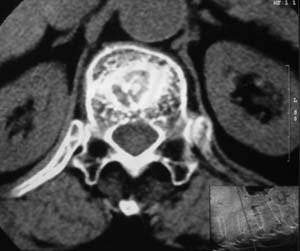

患者,女,72岁,胸背部疼痛3月余,无明显外伤史。曾应用局部封闭、非甾体类止痛药治疗效果不明显,近来疼痛缓解频感背困,平卧缓解,近日行ct检查发现胸12椎体病变,烦请同道发表意见,诊断什么?有何治疗经验!谢谢!!!

标绘图示:第十二胸椎级第一腰椎椎体楔形改变。ct扫描示:第十二胸椎椎体骨质结构紊乱,并可见一囊状低密度影,边缘可见硬化,椎体皮质完整。

考虑:第十二胸椎陈旧性骨折、许莫氏结节。